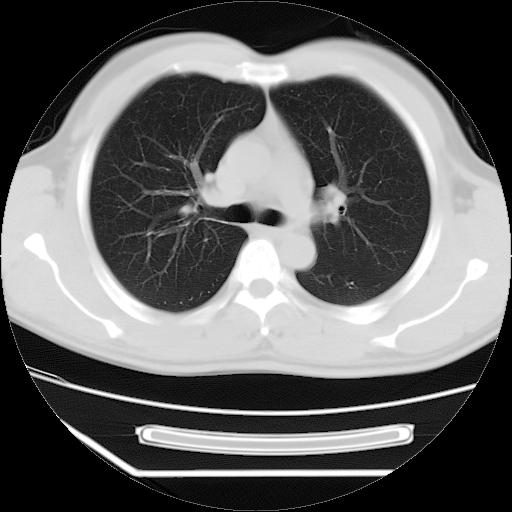

男,38岁,于2009年8月9日晚突发左侧胸痛,今x线提示左下肺阴影,为了明显确诊断,行ct检查,

血常规:嗜酸性细胞增高,单核细胞增高。

病灶发生在下叶,密度均匀,边缘模糊、毛糙,周围血管纹理增强扭曲改变,靠近胸膜处病灶胸膜反应明显。

支持考虑---球形肺炎。

左肺舌叶病变。主体病灶呈类圆形中心密度低,成液化趋势周边班片影分布

考虑肺脓肿

虽然实验室检查支持炎性病变,且病变内有坏死改变(中央呈大片状低密度影),但仍不能掉以轻心,鳞癌也可以有这种影像改变。